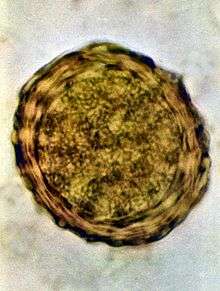

Ascaris lumbricoides is characterized by its great size. Males are 2–4 mm (0.08–0.2 in) in diameter and 15–31 cm (5.9–12 in) long. The male's posterior end is curved ventrally and has a bluntly pointed tail. Females are 3–6 mm (0.1–0.2 in) wide and 20–49 cm (7.9–19 in) long. The vulva is located in the anterior end and accounts for about one-third of its body length. Uteri may contain up to 27 million eggs at a time, with 200,000 being laid per day. Fertilized eggs are oval to round in shape and are 45–75 µm (0.0018–0.0030 in) long and 35–50 µm (0.0014–0.0020 in) wide with a thick outer shell. Unfertilized eggs measure 88–94 µm (0.0035–0.0037 in) long and 44 µm (0.0017 in) wide.[6]